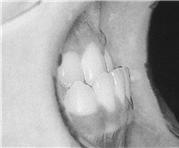

ÈçÈ÷ ¡®ÁÖ°ÆÅΡ¯¼ºÇâ À̶ó°í ¸»ÇÏ´Â III±Þ ºÎÁ¤±³ÇÕÀº À§Åΰú Ä¡¿¿¡ ºñÇØ »ó´ëÀûÀ¸·Î ¾Æ·¡Åΰú Ä¡¿ÀÌ Àüµ¹µÇ¾î ÀÖ´Â °æ¿ìÀÔ´Ï´Ù(±×¸²1-B, ±×¸²4). ¸¶Âù°¡Áö·Î À¯ÀüÀû ¿µÇâÀ» ¸¹ÀÌ ¹ÞÀ¸¸ç »çÃá±â ±Þ¼ºÀå±â¿¡ ¾Æ·¡ÅÎÀÌ ³ª¿À´Â °æ¿ì°¡ ¸¹À¸¹Ç·Î ¼ºÀåÀÌ È°¹ßÇÏ°Ô ÀÌ·ç¾îÁö´Â ½Ã±â¸¦ ³õÄ¡¸é Ä¡·á¸¦ ÇÏ´õ¶óµµ °á°ú°¡ ÁÁÁö ¸øÇÏ¿© ¾Ç±³Á¤¼ö¼úÀÌ ÇÊ¿äÇÒ ¼öµµ Àֱ⠶§¹®¿¡ ÀÜ¿© ¼ºÀåÀ» °í·ÁÇØ¾ß ÇÕ´Ï´Ù. À§ÅÎÀÇ ¿¼ºÀå¿¡ ÀÇÇÑ °æ¿ì¿Í ¾Æ·¡ÅÎÀÇ °ú¼ºÀå¿¡ ÀÇÇÑ °æ¿ì °¢°¢ Ä¡·á¹æ¹ýÀÌ ´Ù¸£¸ç I±ÞÀ̳ª II±Þ ºÎÁ¤±³ÇÕº¸´Ù Ä¡·á¸¦ »¡¸® ½ÃÀÛÇÏ´Â °ÍÀÌ ÁÁ½À´Ï´Ù. ƯÈ÷ À§, ¾Æ·§´Ï°¡ °Å²Ù·Î ¹°¸®´Â ¹Ý´ë±³ÇÕÀÏ °æ¿ì Ä¡¿ÀÇ ±³ÇÕÀÌ À§ÅÎ ¼ºÀåÀÇ Àå¾Ö¿äÀÎÀÌ µÉ ¼ö ÀÖÀ¸¹Ç·Î °¡±ÞÀû Á¶±â¿¡ ÇØ°áÇØÁÖ¾î¾ß ÇÕ´Ï´Ù.